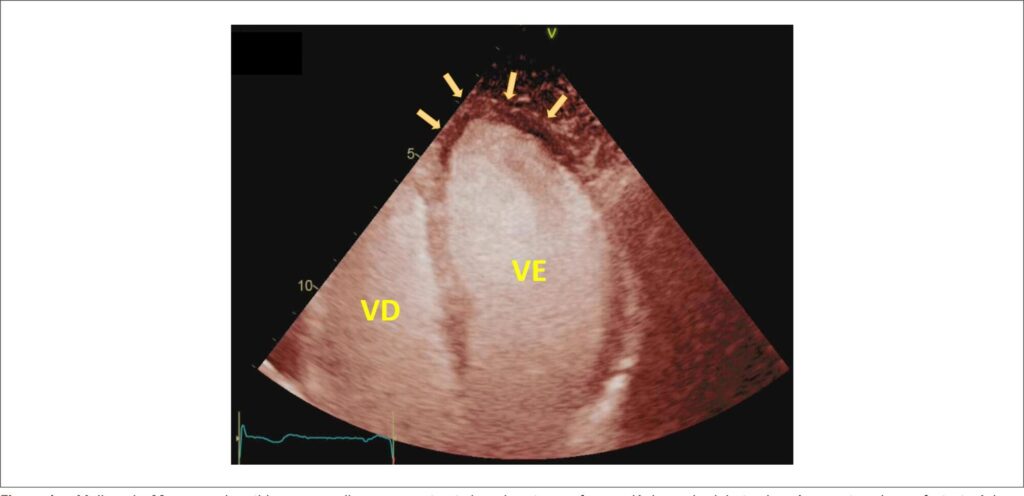

Contraste Ecocardiográfico na Vida Real: Praticidade, Segurança e Custo-efetividade

Após aproximadamente 2 décadas de uso na prática, balizado também em diversos estudos clínicos, pode-se afirmar que os agentes de contraste ecocardiográficos (ACE) são extremamente seguros, seguindo-se as suas recomendações de preparo e administração.– Eventos adversos graves são muito raros, com prevalência aproximada ao redor de 1 a cada 10.000 administrações, sendo as reações anafilactóides os mais frequentes.,- Especificamente com o contraste SonoVue® (hexafluoreto de enxofre) utilizado no Brasil, Furtado, Rassi e colaboradores relataram em seu estudo de segurança uma incidência muito baixa de somente 0,6% de reação alérgica em sua população de 1.099 pacientes que receberam este agente. No geral, as reações alérgicas são imediatas ou em até 30 minutos após administração, de intensidade leve e transitórias. A apresentação mais comum é o surgimento de lesões eritematosas cutâneas e urticária. Neste cenário, contudo, deve-se ter especial atenção para sinais e sintomas respiratórios, como dispneia, estridor laríngeo e broncospasmo, e de progressão para um eventual colapso circulatório, como tontura, palidez e hipotensão, pois se tratam de alertas para instalação do choque anafilático. O paciente deve ser cuidadosamente avaliado e observado, e medidas direcionadas à anafilaxia prontamente instituídas com anti-histamínicos, corticoide e epinefrina, seguindo o protocolo de atendimento local, que deve ter seu pessoal sempre muito bem treinado.